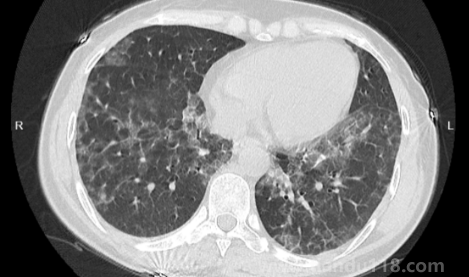

新冠白肺可逆嗎(新冠肺部白化能恢復(fù)嗎) 新冠白肺可逆嗎(新冠肺部白化能恢復(fù)嗎)新冠白肺是比價(jià)常見(jiàn)的一個(gè)癥狀,現(xiàn)在無(wú)論老人還是年輕人如果新冠感染一直咳又不康復(fù)的話,可能會(huì)出現(xiàn)白肺或者肺炎的情況。那么,新冠白肺可逆嗎?84歲老人肺全白有救嗎?一... 小編 2023-01-09 889 #新冠 #白肺

如何自查是否出現(xiàn)白肺(肺白了還能恢復(fù)嗎) 如何自查是否出現(xiàn)白肺(肺白了還能恢復(fù)嗎)白肺是目前很常見(jiàn)的情況,受新冠影響很多老年人都出現(xiàn)了白肺的情況,當(dāng)然也有年輕人會(huì)患上白肺。那么,如何自查是否出現(xiàn)白肺?平時(shí)怎樣保護(hù)自己的肺?一起來(lái)看看天都生活網(wǎng)... 小編 2023-01-06 874 #白肺